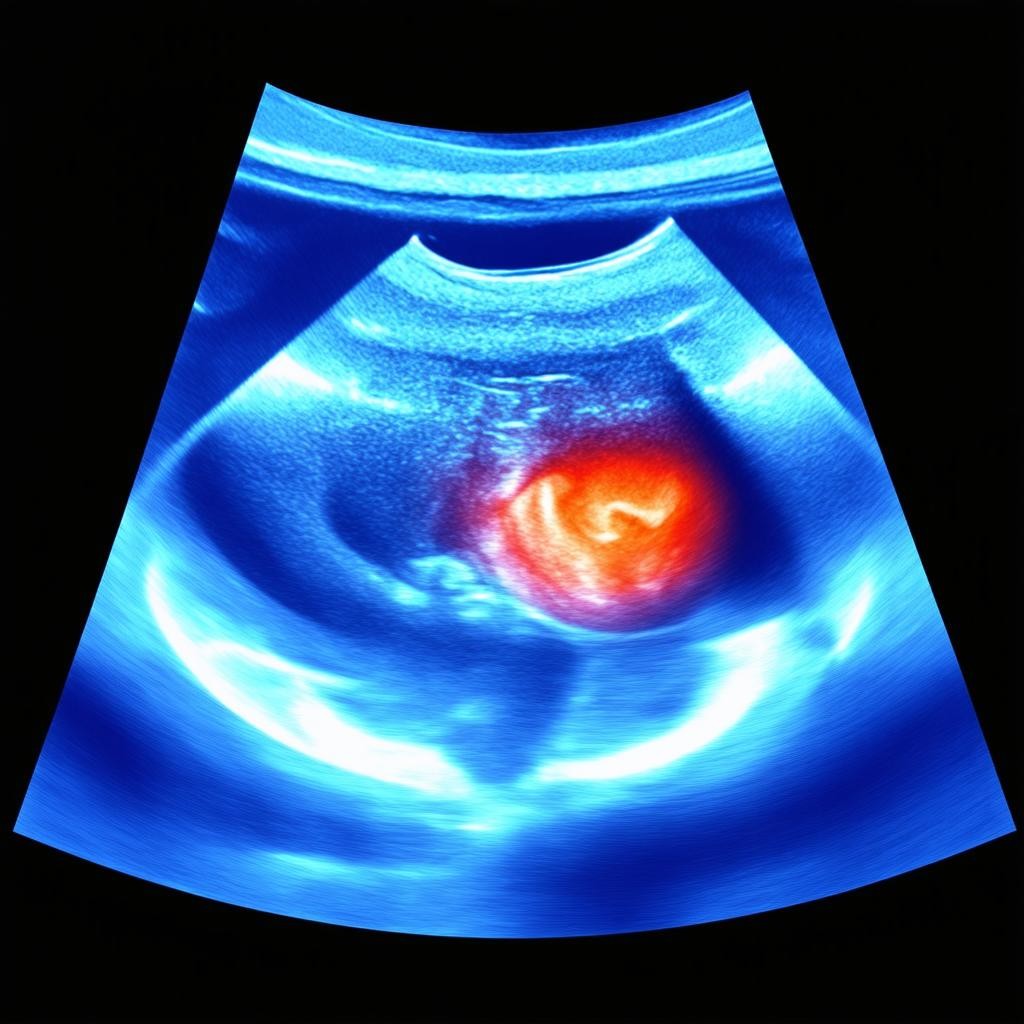

Ультразвуковое исследование сосудов нижних конечностей представляет собой высокоинформативный и абсолютно безопасный метод диагностики, который позволяет оценить состояние венозной и артериальной систем ног. Эта процедура является золотым стандартом в выявлении таких распространенных заболеваний, как варикозное расширение вен, тромбоз глубоких вен, хроническая венозная недостаточность, атеросклероз периферических артерий и многих других патологий. Современное оборудование с функцией цветного допплеровского картирования обеспечивает максимальную точность результатов, что крайне важно для постановки правильного диагноза и назначения эффективного лечения.

В современной диагностической практике применяются несколько видов УЗИ-исследований сосудов нижних конечностей, каждый из которых имеет свои особенности и диагностические возможности. Дуплексное сканирование (УЗДС) сочетает в себе традиционное УЗИ и допплерографию, позволяя одновременно визуализировать сосуды и оценивать характеристики кровотока. Триплексное сканирование добавляет цветовое картирование, что значительно улучшает визуализацию и точность диагностики. Допплерография (УЗДГ) focuses specifically on assessing blood flow velocity and direction, making it particularly valuable for detecting obstructions and evaluating valve function. Each method is selected based on the specific clinical situation and diagnostic objectives.